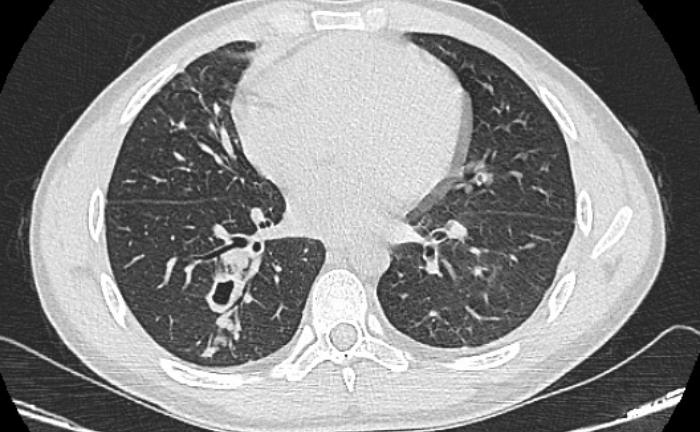

Ho ra máu, đi khám phát hiện sán làm tổ trong phổi

Một năm nay, nam thanh niên mệt mỏi, ho nhiều và ra máu, bác sĩ khám và chẩn đoán nhiễm sán lá phổi.

Sau khi ăn gỏi cua sống được một tháng, nam thanh niên (31 tuổi, ngụ tỉnh Điện Biên) mệt mỏi, sút cân, buồn nôn, được chẩn đoán nhiễm sán lá phổi.